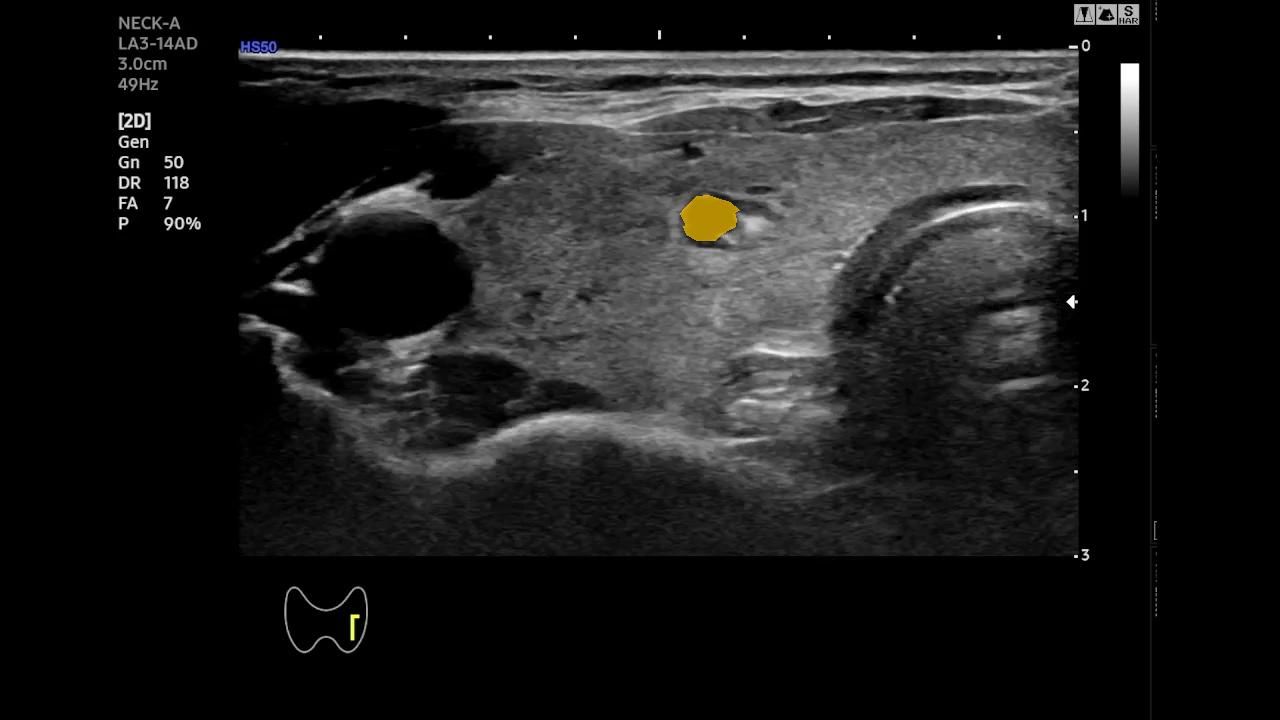

Qualitative Analysis of Temporal Stability- To better highlight the temporal behavior of SAM-2 and EMA-SAM, we visualize predictions at representative frames sampled from a complete RFA sequence. Figure 2 shows a three-row comparison: the first row displays the original ultrasound frames at selected timestamps (with ellipses indicating omitted intermediate frames), the second row shows SAM-2 predictions, and the third row presents EMA-SAM results. As the sequence progresses, SAM-2 occasionally loses the PTMC region when it becomes indistinct or is occluded by RFA bubbles, sometimes mis-segmenting nearby tissue. In contrast, EMA-SAM maintains a coherent segmentation trajectory throughout the sequence. Its confidence-weighted exponential-moving-average pointer preserves a robust latent prototype of the lesion, allowing rapid re-identification and boundary recovery once the PTMC reappears.